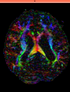

RegLib C03: DWI alignment: align DTI volume with structural reference scan (T2)

RegLib C06:Breast MRI follow-up post treatment

RegLib C08:Intra-subject PET-CT follow-up

RegLib C10: Segmentation via co-registered probabilistic tissue atlas